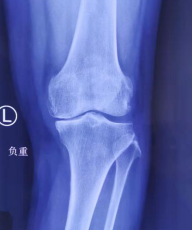

术前x光

关节科邱东新医生接诊后对阿姨进行了详细的检查,发现孙阿姨患有骨性关节炎,膝关节内翻畸形,内侧关节间隙压痛明显,已经严重影响日常生活,符合手术指征。